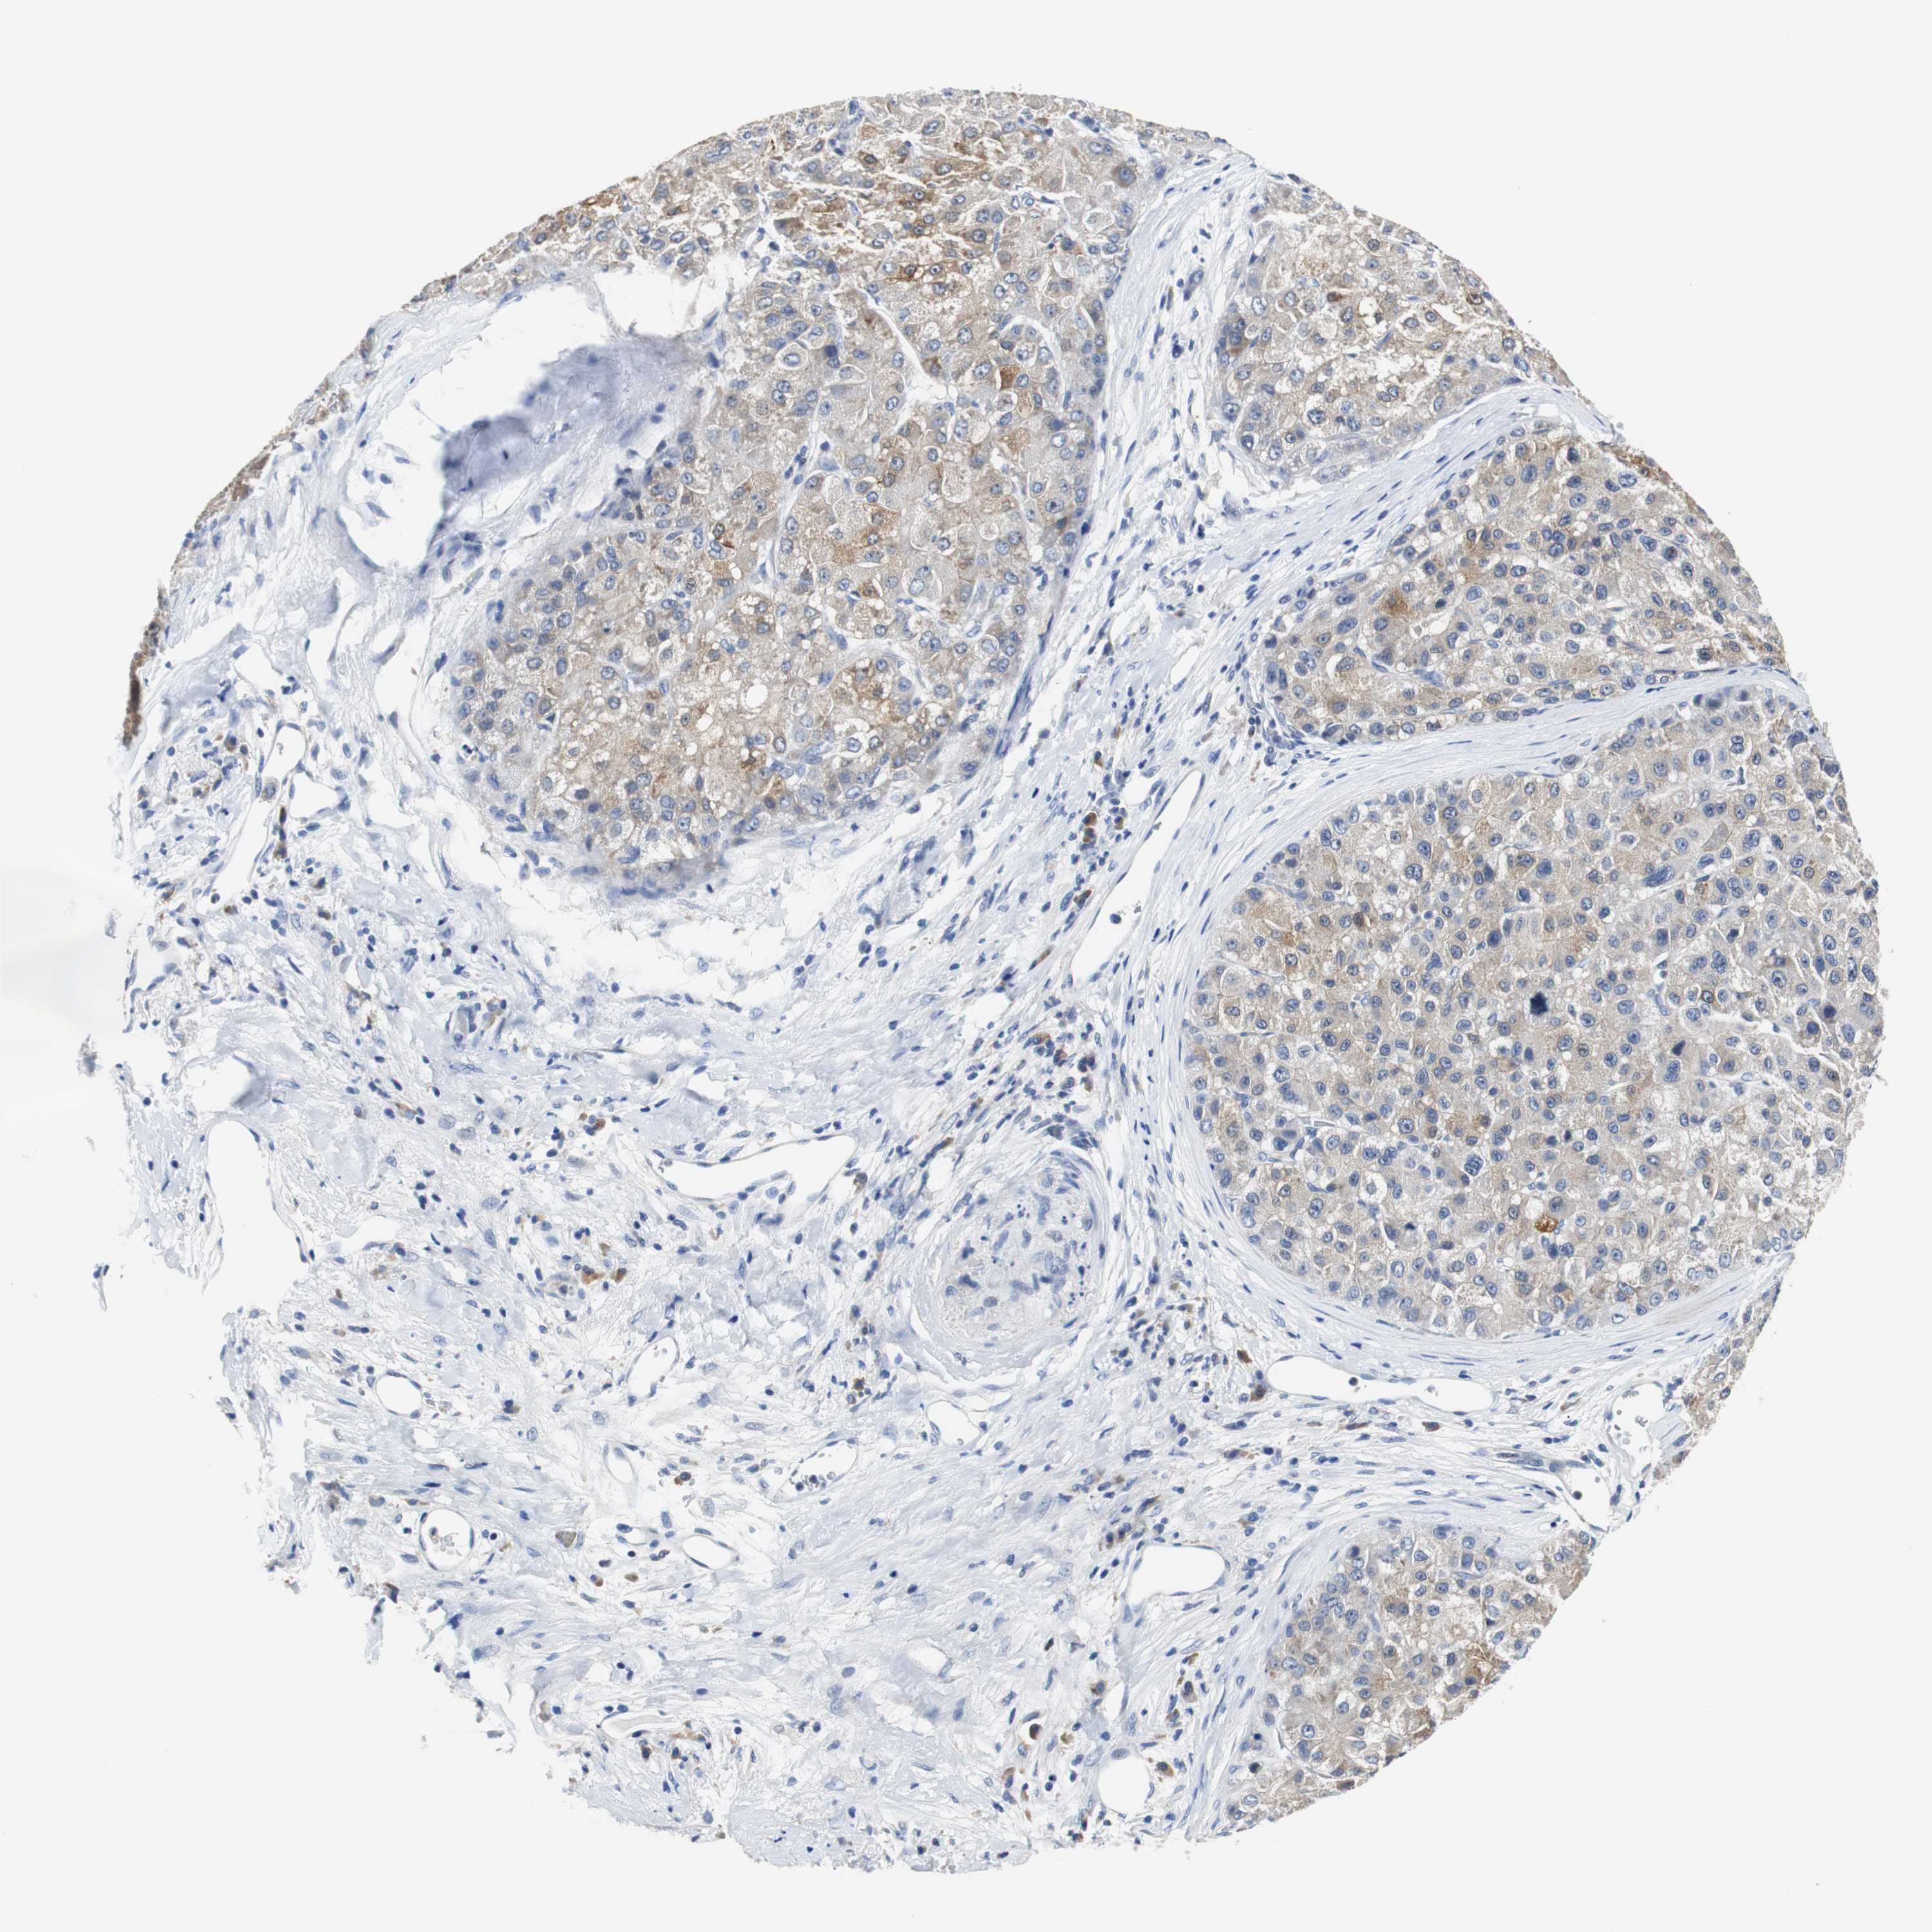

LIVER CANCER - Protein expressioni

A mouse-over function shows sample information and annotation data. Click on an image to view it in a full screen mode. Samples can be filtered based on level of antibody staining by selecting one or several of the following categories: high, medium, low and not detected. The assay and annotation is described here.

Note that samples used for immunohistochemistry by the Human Protein Atlas do not correspond to samples in the TCGA dataset.

Antibody stainingi

Antibody staining in the annotated cell types in the current human tissue is reported as not detected, low, medium, or high, based on conventional immunohistochemistry profiling in selected tissues. This score is based on the combination of the staining intensity and fraction of stained cells.

Each image is clickable and will lead to virtual microscopy that enables deeper exploration of all samples and also displays staining intensity scores, fraction scores and subcellular localization as well as patient and tissue information for each sample.

Antibody HPA006277

Antibody HPA006507

Antibody CAB017027

Staining

High

Medium

Low

Not detected

Intensity

Strong

Moderate

Weak

Negative

Quantity

>75%

75%-25%

<25%

None

Location

Nuclear

Cytoplasmic/membranous

Cytoplasmic/membranous,nuclear

Cholangiocarcinoma

Carcinoma, Hepatocellular, NOS